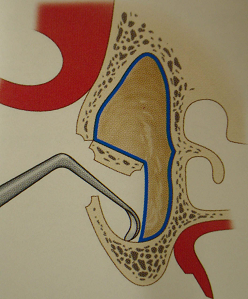

明日は久しぶりにサイナスリフトのオペが入っている。しょっちゅうあるわけではないので、オペ前には感覚を戻すために、必ず生卵で練習している。生卵で100発100中うまくいけば、臨床では100パーセントうまくいくという話もあるが、臨床の方がいろんな制約があって(出血するとか、見ずらいとか)、結構大変だ。高速回転の昔ながらの機械で、生卵の中の膜を破らずに窓開けをする。生卵の殻が実際の臨床では顎の骨に相当する。最近はピエゾサージェリーなる超音波の機械がはやってきて窓開けも楽ちんになったという話をよく聞く。今日バイトに来てたN先生に聞いたら、「医科歯科大インプラント治療部ではピエゾから昔のやり方に戻った」とのこと。やはり手の感覚に勝るものは無いのか?2002年にミシガン大学に行ってまで覚えたこの手術。患者さんごとに解剖学的構造が異なるので、ちょっと慣れたからと言って舐めてはかかれない。前の晩は妙に緊張する。さあ早く寝よう。

生卵でサイナスリフトの練習